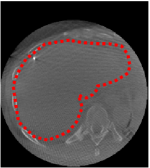

An example of CT/CBCT and MR/CBCT registration results are shown in figures 3 and 4, respectively. For both cases, the CBCT image (first column) was acquired intra-operatively after needle insertions and was employed as a reference for image registration. The pre-operative image is displayed before registration (second column), after PM-EA (third column) and after PM-EA+Evo (fourth column). The occurrence of patch shifts is reported for each spatial direction in panels (m–o): for each histogram, the shift with maximal occurrence is shown by the red dashed line. For panels (a–l), a ROI — manually defined on the CBCT image/encompassing the liver — is shown using red dash lines. Our visualization shows an improved correspondence of the contour of the liver with the manually defined liver boundary when the PM-EA solution is employed (see 3(c,g,k) and 4(c,g,k)). Moreover, an even better correspondence of the contour is observable using the PM-EA+Evo solution (see 3(d,h,l) and 4(d,h,l)).

Trans.

[X-Y]

CBCT

(a)

MRI / No registration

(b)

MRI / PM-EA

(c)

MRI / PM-EA+Evo

(d)

Sag.

[X-Z]

(e)

(f)

(g)

(h)

Cor.

[Y-Z]

(i)

(j)

(k)

(l)

(m)

(n)

(o)